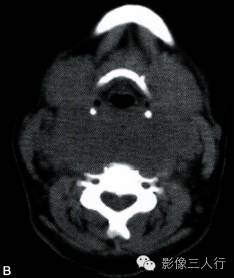

A~C.CT平扫横断面;D~F. CT增强横断面;G. HE×40

双侧甲状腺、颌下腺及咽淋巴环见多发结节融合状软组织影,边界不清,可见包膜,病灶密度欠均匀,内可见线样分隔,未见明显坏死及钙化,双颈各区可见大小不等的淋巴结,边界欠清,密度较均匀(图A~C)。增强横断面(图D~F)扫描双侧甲状腺、颌下腺及咽淋巴环病灶包膜及分隔可见明显强化,双颈淋巴结可见较明显强化。